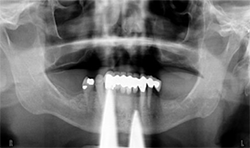

A 71-year-old male presented with a full maxillary denture and retained lower left canine and lower right first premolar (Fig. 3). He desired a semi-permanent solution to improve fit, function of upper and replace all missing teeth on the lower. An initial panoramic radiograph was taken for surgical and restorative planning purposes. The patient and doctor discussed options and it was decided  a new maxillary full denture and a fixed hybrid prosthesis on the lower arch would be acceptable treatment options.

Fig.3

The patient’s medical history was evaluated for a mandibular fixed hybrid prosthesis using four Bicon implants and a TRINIA substructure. A CBCT revealed adequate bone for implantation and reviewed clinically after properly dissecting the mental nerve to avoid paresthesia. Four implants were placed through the anterior to increase the AP spread. Mandibular full thickness mucoperiosteal flap across the ridge was released and mental foramen were identified bilaterally. The posterior implant was placed 5 mm anterior to the mental foramen. All sites were prepared, checked for parallelism and enlarged to receive four implants each 4 mm x 8 mm with a 2.5 well (Fig. 4).